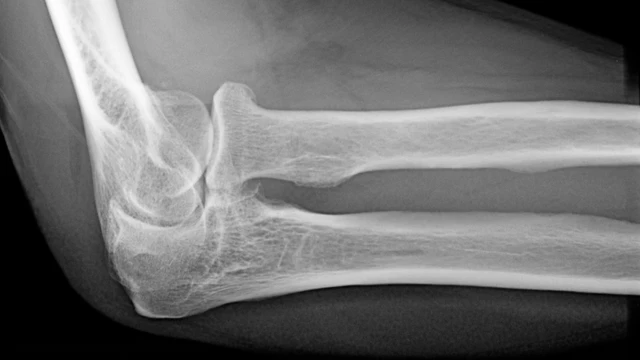

X quang khớp khuỷu là một phương pháp chẩn đoán hình ảnh quan trọng trong y khoa, giúp phát hiện sớm các vấn đề về khớp khuỷu như viêm khớp, gãy xương, hay tổn thương mô mềm. Phương pháp này không chỉ hỗ trợ bác sĩ trong việc xác định chính xác tình trạng bệnh lý mà còn góp phần xây dựng phác đồ điều trị hiệu quả. Đây là một công cụ không thể thiếu trong việc bảo vệ sức khỏe và nâng cao chất lượng sống của bệnh nhân.